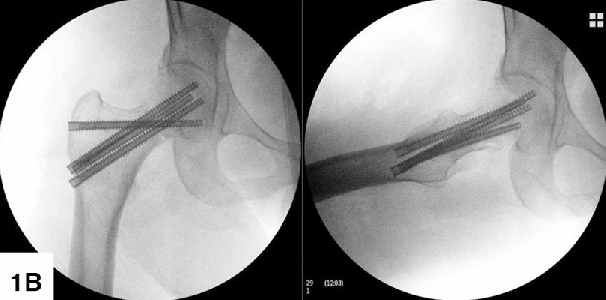

2. 全螺纹钉交叉固定 (FTS / Crossed Screw) —— “长度维持派”

• 原理: -

• 全螺纹(Length-stable): 螺钉同时咬住股骨头和股骨颈/粗隆,消除了滑动,目的是“锁死长度”,防止股骨颈短缩。 -

• 交叉布局(Alpha/F-technique): 就像搭建房梁(桁架结构)。关键是增加一枚螺钉,其轴向与剪切方向接近垂直(理想为90°),力学重构,抑制了剪切位移。这是平行钉做不到的。 -

两种交叉布局方式对比 -

(阿尔法固定,因为形状类似手写的α;F技术也适用于半螺纹钉) -